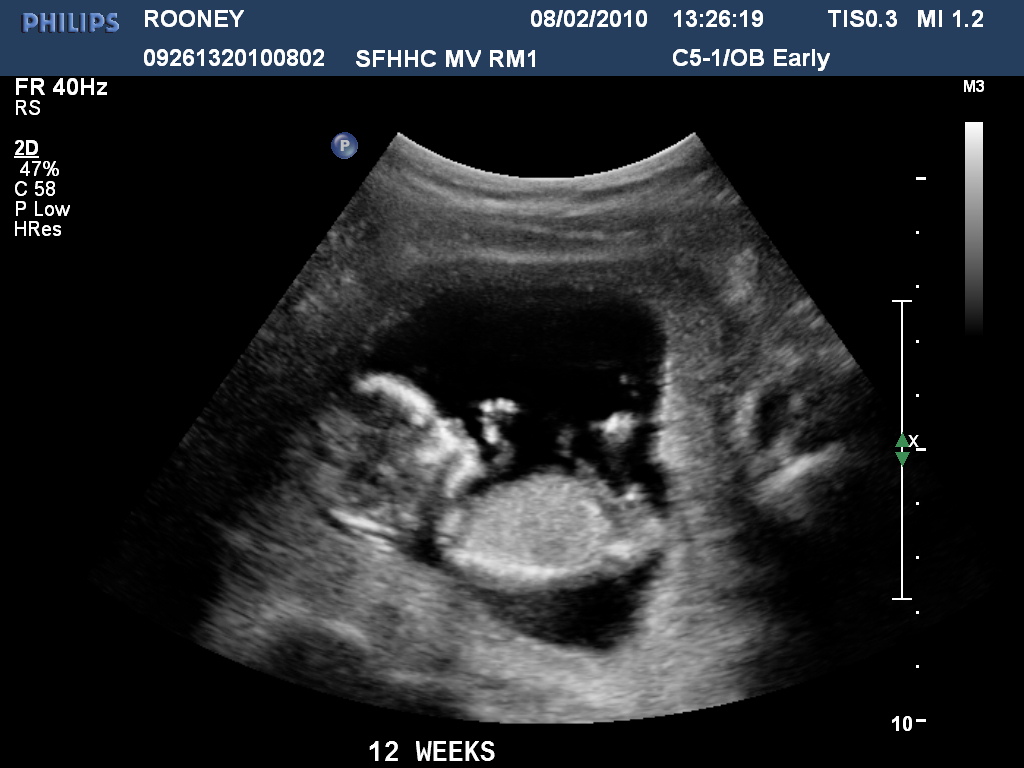

12 Week Pregnancy Ultrasound Pregnancy Test Before 12 Week Scan This is called the dating scan. If you're pregnant in england you'll be offered an ultrasound scan at around 10 to 14 weeks of pregnancy. Ensure that antenatal care can be started in a variety of straightforward ways, depending on women's needs and. When will i have an ultrasound scan? You’ll be offered a test for thalassaemia, an inherited blood. Pregnancy Test Before 12 Week Scan.

Normal 12 Week Ultrasound Pregnancy Test Before 12 Week Scan The screening test for sickle cell and thalassaemia should be offered as early as possible before 10 weeks of pregnancy. An early pregnancy scan (dating or booking scan). You should be offered at least 2 scans: All pregnant women in england are offered a screening test for down’s syndrome, edward’s syndrome and patau’s syndrome. This is called the dating scan.. Pregnancy Test Before 12 Week Scan.

Pregnancy Ultrasound Pictures 12 Weeks Pregnancy Test Before 12 Week Scan You’ll be offered a test for thalassaemia, an inherited blood disease, and a combined screening test for down, edwards’ and patau’s syndrome if you’re more than. An early pregnancy scan (dating or booking scan). The screening test for sickle cell and thalassaemia should be offered as early as possible before 10 weeks of pregnancy. Some pregnancy screening tests should take. Pregnancy Test Before 12 Week Scan.

12 Weeks Pregnant Ultrasound Pregnancy Test Before 12 Week Scan Ensure that antenatal care can be started in a variety of straightforward ways, depending on women's needs and. An early pregnancy scan (dating or booking scan). This is called the dating scan. When will i have an ultrasound scan? You’ll be offered a test for thalassaemia, an inherited blood disease, and a combined screening test for down, edwards’ and patau’s. Pregnancy Test Before 12 Week Scan.